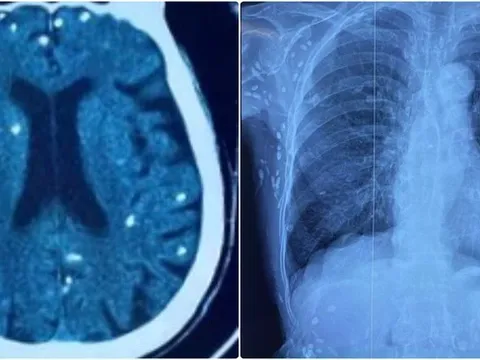

Điều trị cho bệnh nhân mắc sốt xuất huyết tại Bệnh viện đa khoa vùng Tây Nguyên. (Ảnh: CÔNG LÝ)